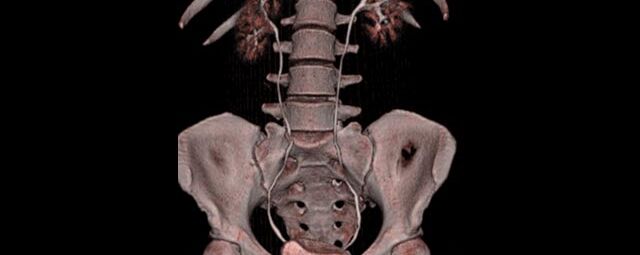

Wirbelsäule

• Darstellung von Frakturen, Tumoren und Bandscheibenveränderungen

Spezielle Software ermöglicht jetzt zum Beispiel:

• besonders hochauflösende, strahlendosissparende Darstellung aller Skelettstrukturen

• mehrdimensionale Darstellung vasculärer Strukturen mit zahlreichen Auswertungstools